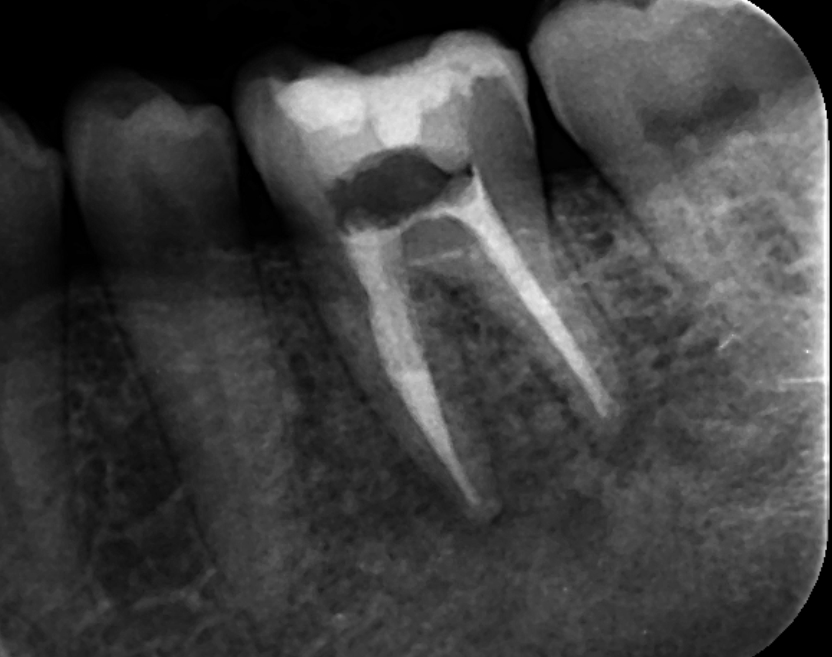

下顎第一大臼歯の根管充填時のレントゲン写真です。細菌感染を残さないよう、根管の隅々まで丁寧に清掃を行い、根の先まで根管充填を行いました。